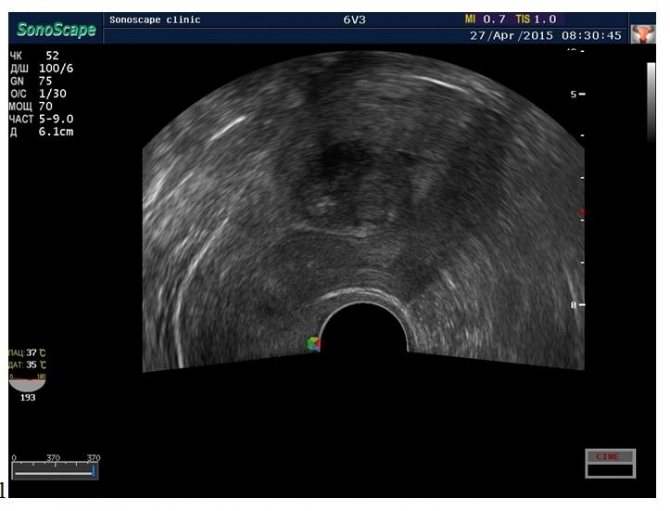

- Ультразвуковое исследование (УЗИ). Проводится с целью определения локализации и структуры миомы.

- Трехмерная эхография. Показание к проведению – точное выявление локализации и размеров миоматозных узлов.

- Допплерография. Проводится для оценки интенсивности кровотока в области опухоли, что помогает определить прогноз заболевания.